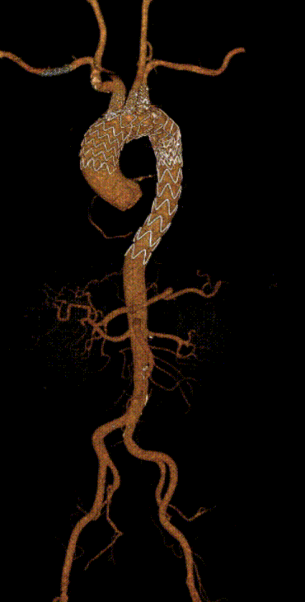

术前 CTA

术前CTA